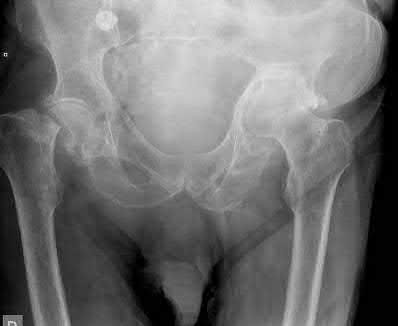

Question 1:

A 12-year-old obese boy presents with vague left thigh and knee pain. He is diagnosed with a Slipped Capital Femoral Epiphysis (SCFE) as seen in similar clinical scenarios. During percutaneous in-situ fixation, unrecognized penetration of the guide wire into the hip joint occurs. What is the most likely specific complication resulting from this technical error?

Correct Answer: Chondrolysis

Explanation:

Chondrolysis is a severe complication of SCFE characterized by rapid destruction of the articular cartilage. While it can occur idiopathically, its most established iatrogenic cause is unrecognized intra-articular hardware penetration. The 'approach-withdraw' fluoroscopic technique is required during pinning to assure pins are entirely intraosseous. Avascular necrosis (AVN) is usually due to damage to the epiphyseal blood supply (retinacular vessels) secondary to the initial displacement, forceful closed reduction, or posterosuperior pin placement.